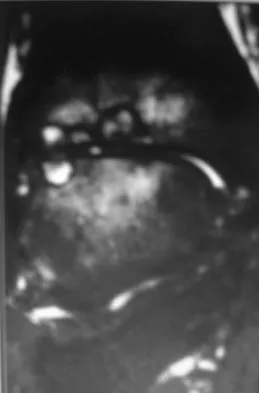

A 30-year-old man has had intermittent swelling of his right ankle for the past 6 months. He denies any history of trauma. Radiographs reveal osteolytic changes on both sides of the joint. An axial CT scan and a T2-weighted MRI scan are shown in Figures 40a and 40b. He undergoes surgical excision. An intraoperative photograph and a biopsy specimen are shown in Figures 40c and 40d. What is the most likely diagnosis?